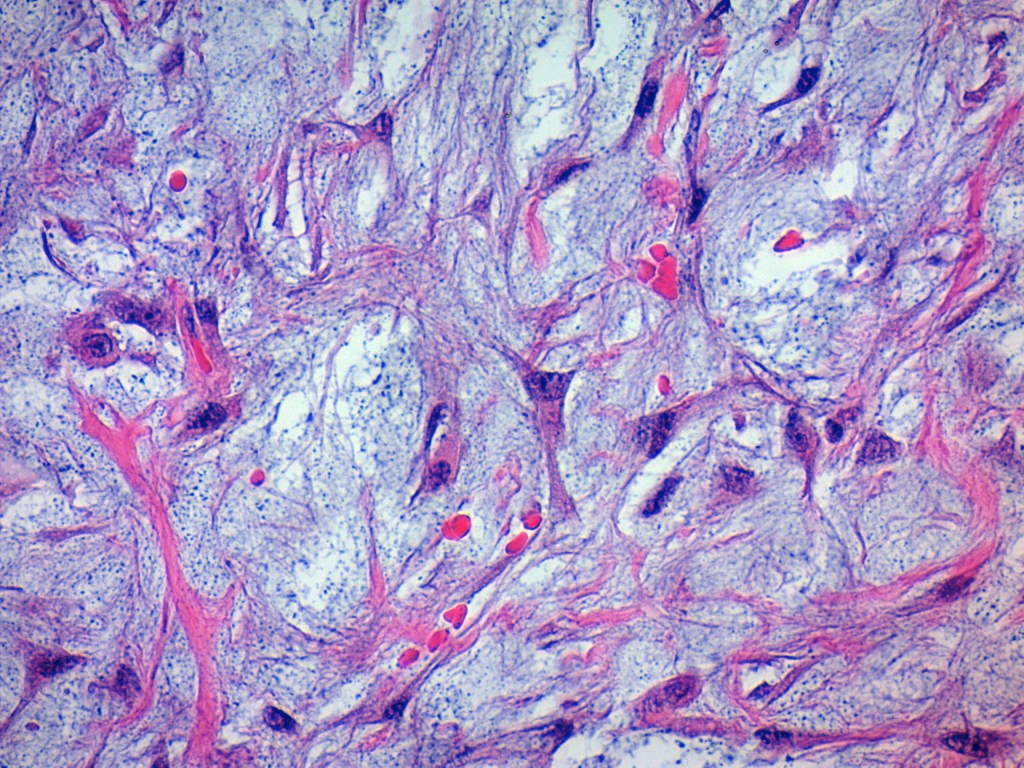

- Well-circumscribed but unencapsulated.

- Borders are well demarcated but may show focal infiltration.

- Composed of plump fibroblasts with eosinophilic cytoplasm, arranged in a short fascicular pattern.

- Abundant loose to myxoid stroma.

- Occasional thick, «keloidal» type collagen.

- Extravasated erythrocytes.

- Histiocytes.

- A few osteoclast-type giant cells—just because.